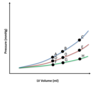

Point 0 represents LV End Diastolic Pressure (LVEDP) at baseline.

Which point best represents the LVEDP in a stiff left ventricle?

The blue line in general

A stiffer left ventricle would result in increased pressure at every volume (especially higher volumes), becuase the ventricle cannot stretch as well to accomodate volume